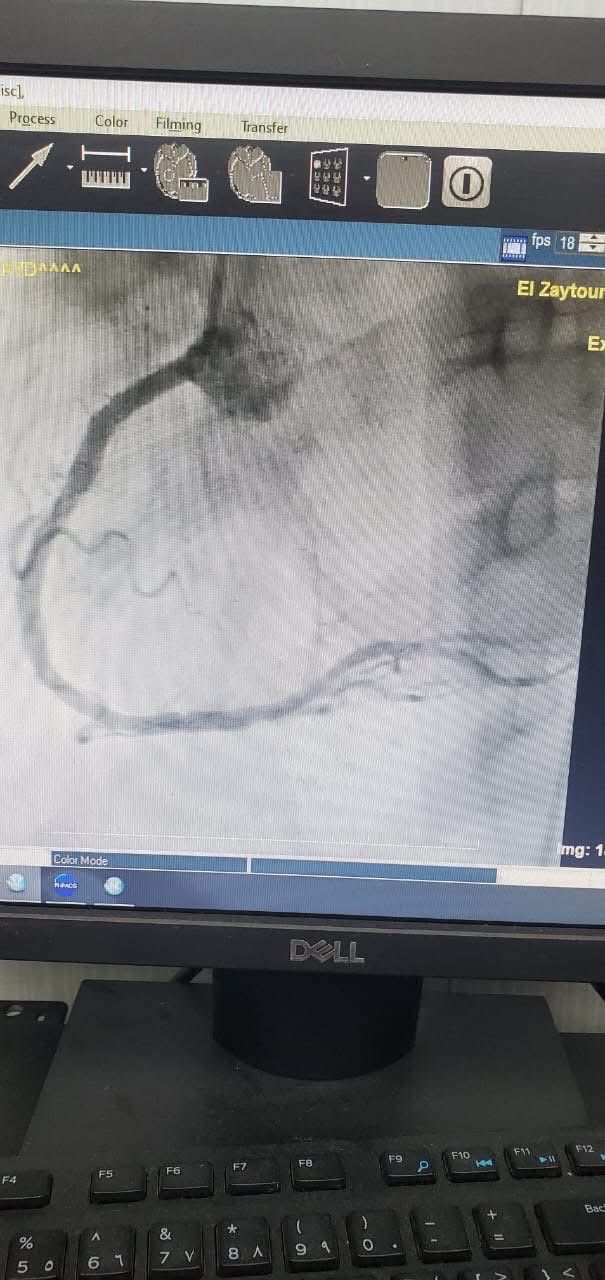

وأشار إلى أنه تم استخدام كمية قليلة من صبغة الأشعة للكشف عن الشرايين، ثم نقل المريض مباشرة إلى القسطرة، حيث نجح الفريق في فتح الشريان المسدود وتركيب دعامتين وتوسيع الشريان واستخدام البالون، مع وضعه على جهاز التنفس الصناعي طوال الإجراء.